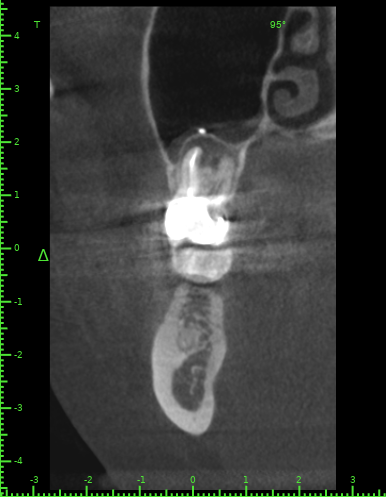

Katya88 Опубликовано 28 июля, 2021 Поделиться Опубликовано 28 июля, 2021 Мой стоматолог терапевт советует удалить, так как там кисты, а ортопед советует найти того, кто займется лечением. КТ прилагаю https://drive.google.com/file/d/1Z-neEH63BszTXxa8bAOG1tgsrIrsqrVK/view?usp=drive_web Ссылка на комментарий

Женька Опубликовано 28 июля, 2021 Поделиться Опубликовано 28 июля, 2021 2.6 2.7 3.7 На 3.5 и 1.5 стоит обратить внимание 1.5 1 Ссылка на комментарий

Женька Опубликовано 28 июля, 2021 Поделиться Опубликовано 28 июля, 2021 54 минуты назад, Katya88 сказал: 1.5 менять коронку как минимум снять существующую конструкцию и посмотреть клинически на зуб(ы). 1.5 на КТ выглядит удручающе. По остальным, я бы поддержал ортопеда и попытался зубы сохранить. Пусть коллеги меня поправят. 1 1 Ссылка на комментарий